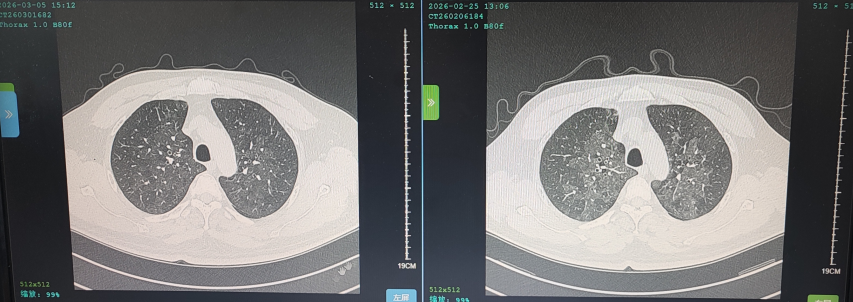

花鸟相伴本是生活雅趣,但鸟类羽毛碎屑、排泄物及粉尘中潜藏的有害物质,却可能悄然成为肺部健康的“隐形杀手”。这类疾病起病隐匿、症状不典型,极易被误诊或漏诊,严重时甚至可迅速进展为重症肺炎、呼吸衰竭,危及生命。近日,葫芦岛市第二人民医院呼吸与危重症医学科连续收治多例与接触鸟类密切相关的肺部疾病患者,为广大“养鸟一族”敲响警钟。 病例一:久咳不愈竟致呼吸衰竭 真凶竟是“养鸟过敏” 50岁的刘先生咳嗽、咳痰、气短两个月,严重时彻夜难眠,辗转求医无果,入院时已确诊I型呼吸衰竭。肺部影像学检查显示,双肺广泛存在磨玻璃影,局部已呈现“白肺”表现。此时,鉴别是感染性还是非感染性因素,成为诊断的关键。 ↑氧分压<60mmHg、二氧化碳氧分压正常、呼吸频率异常,呼吸衰竭 ↑相关检验项目正常,排除感染性因素 宋刚主任细致追问病史,发现其长期接触鸟类,结合支气管镜检查排除常见感染,最终明确诊断为外源性过敏性肺泡炎(过敏性肺炎),合并急性喘息性支气管炎。病因正是吸入鸟类羽毛及排泄物中的特异性蛋白过敏原,导致肺部过敏性炎症损伤。在脱离过敏原、接受经鼻高流量等规范治疗后,刘先生症状迅速缓解,顺利康复出院。 ↑左侧为治疗后肺部影像,右侧为治疗前肺部影像,肺炎明显减轻 病例二:高龄重症合并多重基础病 幕后黑手竟是鹦鹉热衣原体 86岁的杨大爷持续高热3天,体温达39℃,入院时已出现严重呼吸衰竭。更棘手的是,患者有20年再生障碍性贫血病史,白细胞、血小板极低,属典型免疫抑制,极易感染罕见病原菌。因血小板过低,行支气管镜检查出血风险极高。科室另辟蹊径,采用痰液NGS检测,精准锁定了致病元凶——鹦鹉热衣原体,这是一种经鸟类传播的非典型病原菌。 ↑鹦鹉热衣原体检测结果 ↑患者再生障碍性贫血,白细胞、血小板极低 诊断明确,治疗却面临两难:患者合并下肢静脉血栓,本应进行抗凝治疗,却因血小板严重低下受限。医疗团队综合研判、分层施策,严密监测血氧及肺栓塞风险,同步控制感染,并多次输注血小板、白蛋白及免疫球蛋白加强支持治疗。经综合救治,杨大爷病情好转,顺利出院。 ↑左侧为治疗前影像,右侧为治疗后影像,感染明显好转 病例三:体检发现肺部团块影 不是肺癌是真菌 患者养鸟多年,体检时发现右下肺团块状阴影,家属一度担心是肿瘤。但宋刚主任对比前年肺部影像,凭借丰富经验判断:恶性肿瘤在一年内长成如此大的团块相对少见,且病灶周围有典型晕征,高度怀疑是隐球菌肺炎——这是一种真菌性感染病,致病菌常寄生于鸟类粪便中。随后通过隐球菌荚膜多糖抗原检测,快速明确隐球菌肺炎诊断,规范抗真菌治疗后,病灶逐步缩小,病情控制稳定。 ↑隐球菌肺炎疗程较长,左侧为治疗后1个月的肺部影像,右侧为治疗前肺部影像,可见左侧晕征较右侧减轻 专家提醒:养鸟有风险 呼吸不适须警惕 宋刚主任表示,日常养鸟需做好防护: ☑ 注意环境卫生,保持通风干燥,控制粉尘; ☑ 定期清洁鸟笼与排泄物,清理时佩戴口罩、手套,避免直接接触; ☑ 老人、免疫低下、基础病较多者更需格外警惕。若出现长期咳嗽、气短、发热等症状,且有鸟类接触史,务必及时到专业呼吸科就诊,避免误诊漏诊。 我院呼吸与危重症医学科作为市级重点专科,致力于各类重症肺炎、呼吸衰竭、慢性气道疾病、哮喘等疾病的鉴别及规范化治疗,复杂疑难重症诊疗能力突出。同时携手中国医科大学附属第一医院,顶尖呼吸科专家每月定期来院出诊,让滨城百姓在家门口就能享受到省级优质医疗服务,为群众呼吸健康筑牢坚实屏障。 人民医院 人民名医 宋刚 主任医师 ·葫芦岛市第二人民医院呼吸与危重症医学科主任 ·辽宁省生命科学学会东北呼吸与危重症医学(PCCM)分会辽宁省基层委员会副主任委员 ·辽宁省细胞生物学学会放射粒子治疗专业委员会理事 ·辽宁省抗击新冠肺炎疫情先进个人 ·辽宁省预防医学会第一届吸烟相关疾病防治专业委员会委员 ·葫芦岛市劳动鉴定委员会专家库成员 ·葫芦岛市医学会呼吸内科学分会第三届委员会副主任委员 专业特色:擅长呼吸系统疑难及急危重患者的救治,如急慢性支气管炎、支气管哮喘、慢性阻塞性肺疾病、肺炎、肺栓塞、肺癌、间质性肺疾病、睡眠呼吸暂停综合征等,尤其擅长有创无创机械通气、支气管镜下相关检查及治疗(TBNA、气道支架置入术、球囊扩张等)、全肺灌洗术等领先技术,发表国家级期刊多篇。 出诊时间:每周二、周四全天 出诊地点:门诊二楼东侧35诊室 咨询热线:0429-8010115